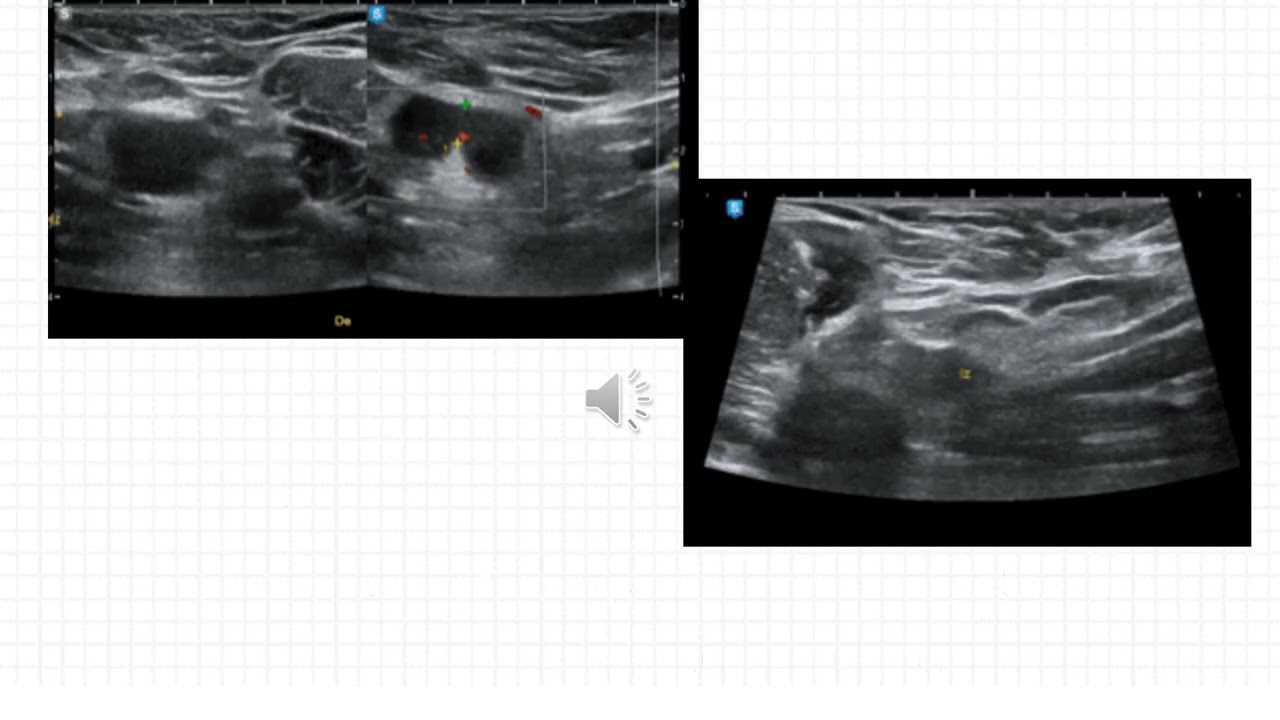

Caso del Mes n°229 Octubre 2025 "Enfermedad por Arañazo de Gato" Dra. Chicala López Virginia